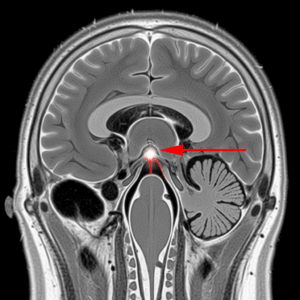

איך בנוי חלל האף והסינוסים

- מחיצה באמצע ( מפרידה בין צד ימין לשמאל)

- בליטות בצדדים (קונכיות) – יש 3 בכל צד: תחתונה, אמצעית ועליונה

- חללי אויר סמוכים ומחוברים לאף (סינוסים)

- כדי לנשום מהאף צריך שיהיה מעבר בין המחיצה לקונכיות בשני הצדדים

- סטיית מחיצה – קיימת אצל מעל מ 50% מהאוכלוסיה בדרגה כלשהי